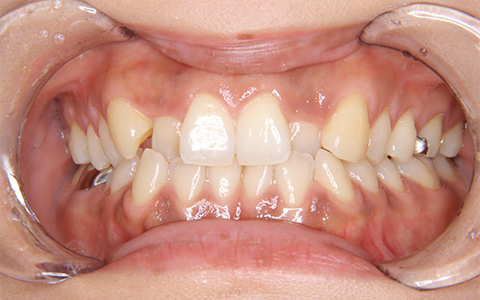

CASE.1

治療前

治療後

施術内容 上の2番目の歯が内側にあることがお悩みでご来院(33歳)。前歯部の叢生・交叉咬合に対するマウスピース型矯正装置(インビザライン)による非抜歯治療

治療期間 1年1ヶ月(通院7回)

費用 880,000円

リスク・副作用 歯が動く痛み、歯髄壊死、歯根吸収、歯肉退縮、リテーナーを使用しないことによる後戻り